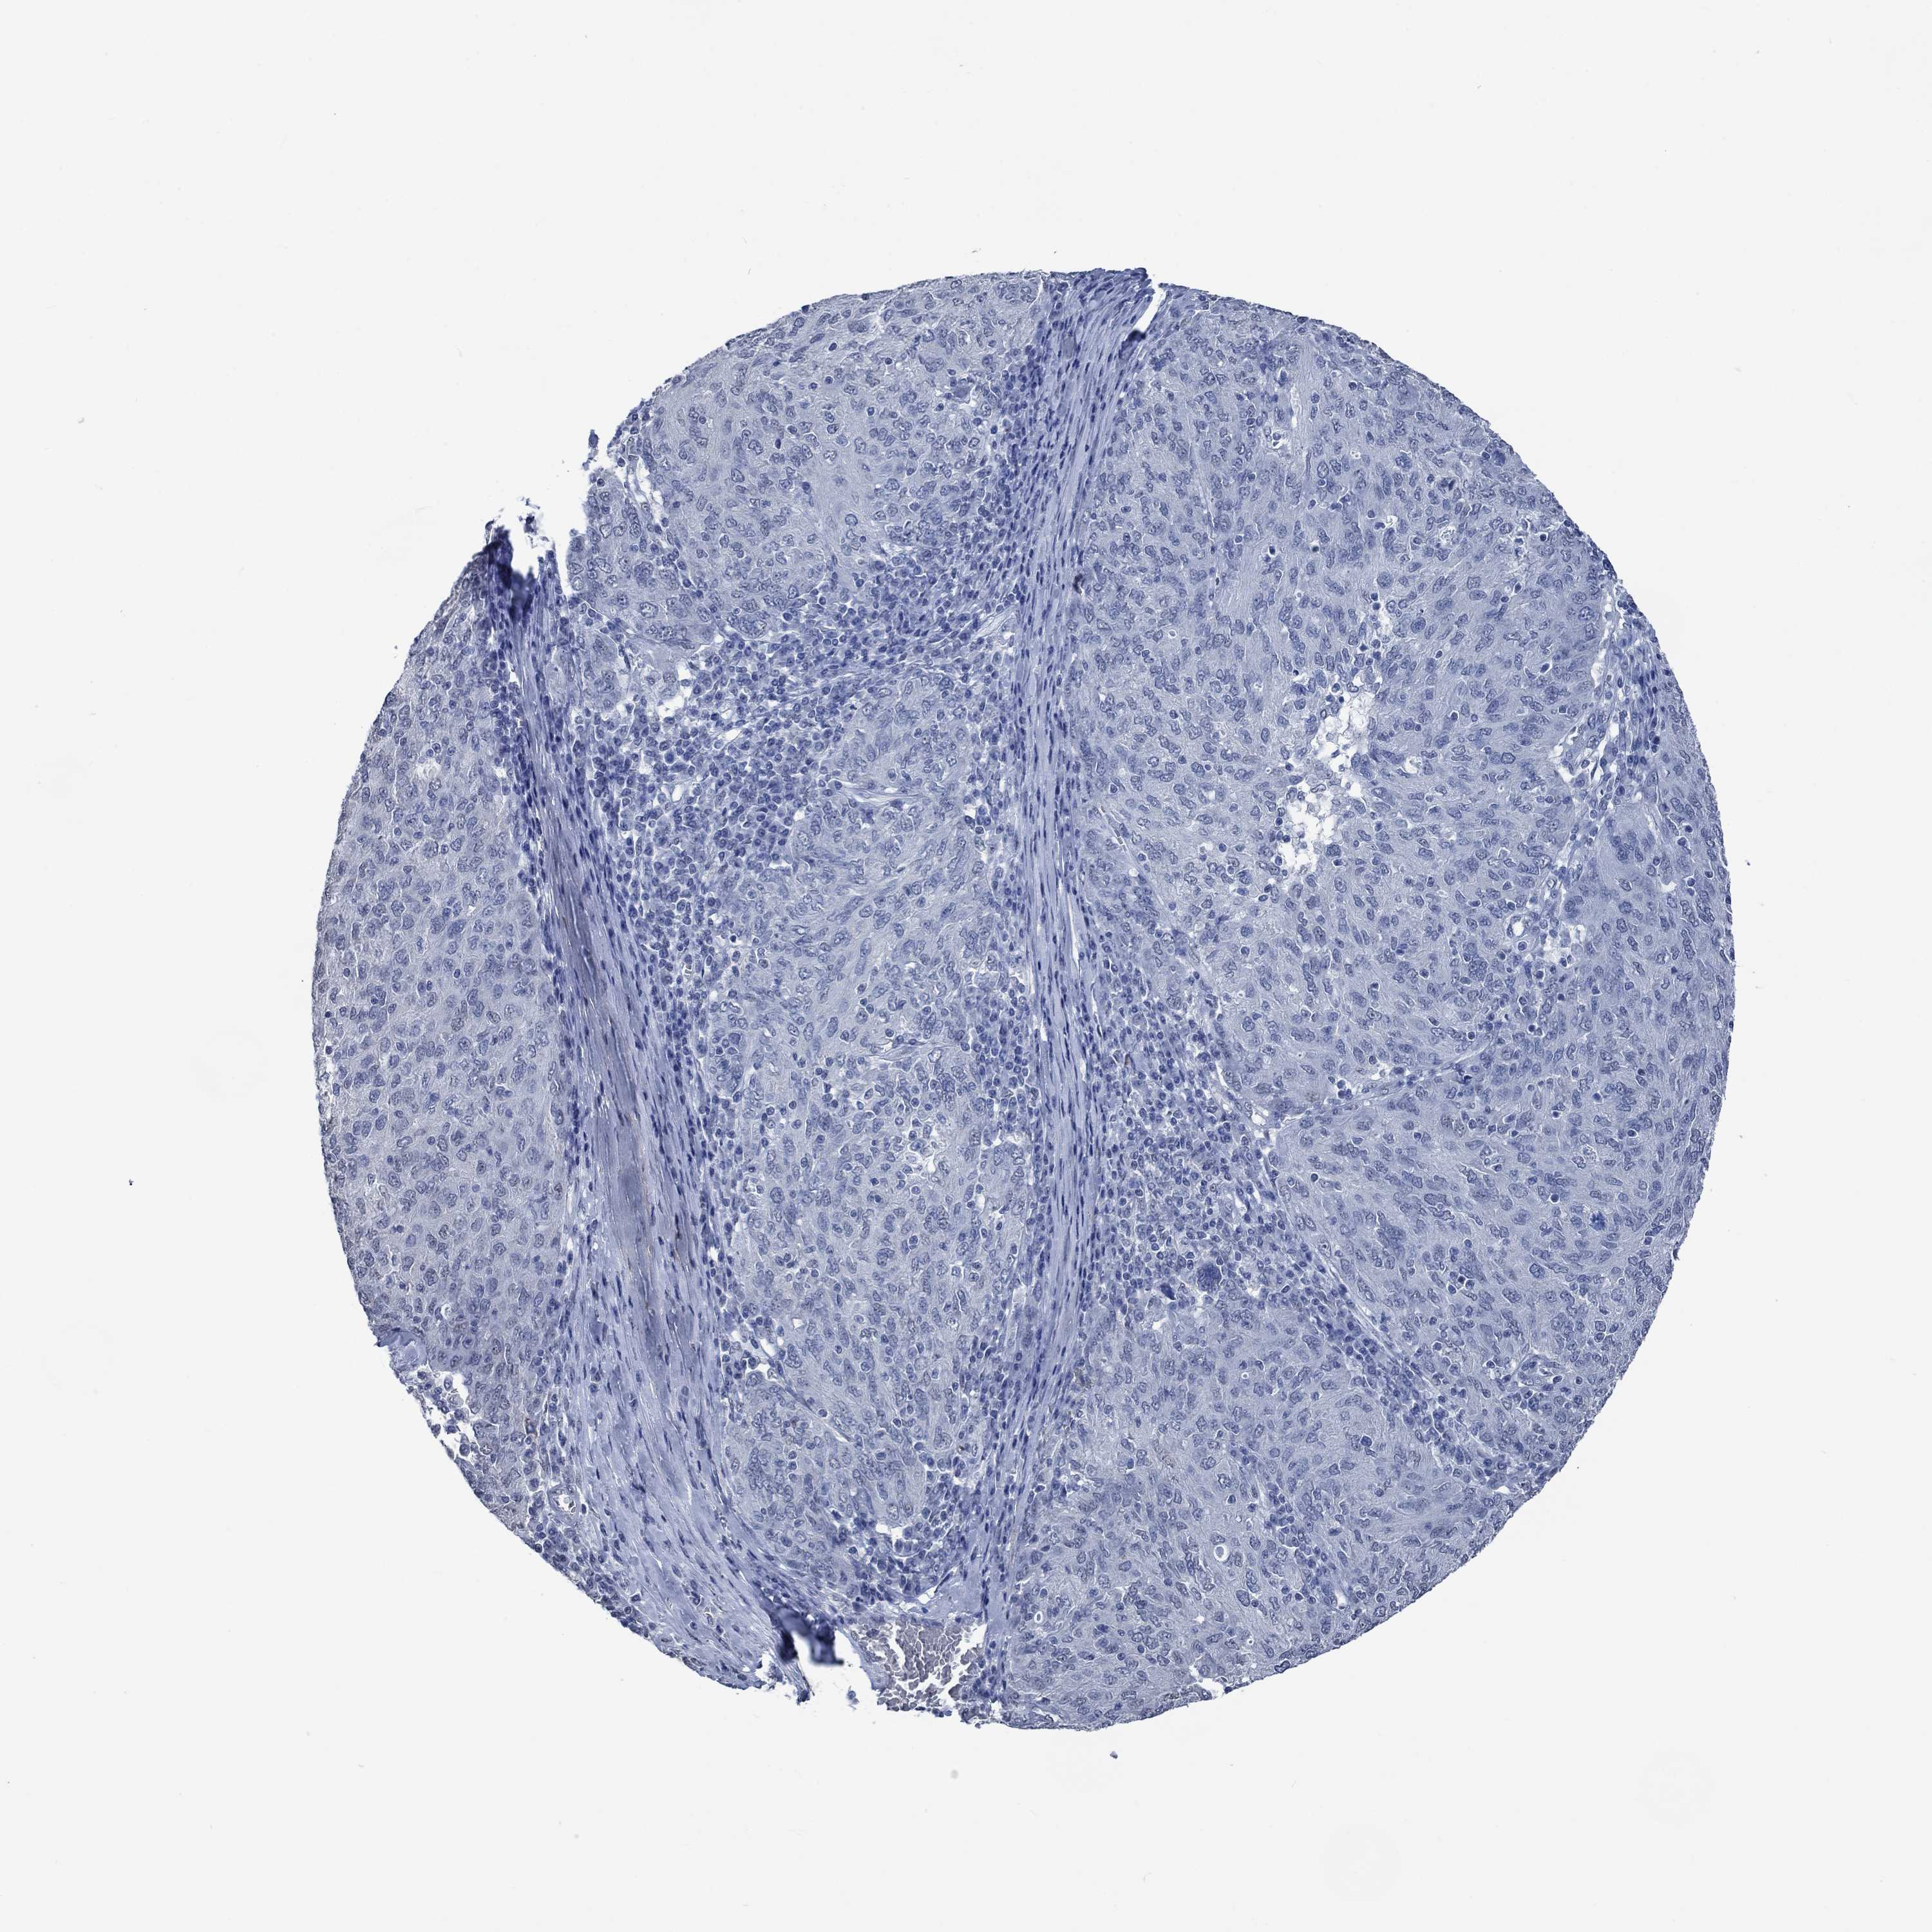

OVARIAN CANCER - Protein expressioni

A mouse-over function shows sample information and annotation data. Click on an image to view it in a full screen mode. Samples can be filtered based on level of antibody staining by selecting one or several of the following categories: high, medium, low and not detected. The assay and annotation is described here.

Note that samples used for immunohistochemistry by the Human Protein Atlas do not correspond to samples in the TCGA dataset.

Antibody stainingi

Antibody staining in the annotated cell types in the current human tissue is reported as not detected, low, medium, or high, based on conventional immunohistochemistry profiling in selected tissues. This score is based on the combination of the staining intensity and fraction of stained cells.

Each image is clickable and will lead to virtual microscopy that enables deeper exploration of all samples and also displays staining intensity scores, fraction scores and subcellular localization as well as patient and tissue information for each sample.

Antibody HPA021186

Antibody HPA065801

Staining

High

Medium

Low

Not detected

Intensity

Strong

Moderate

Weak

Negative

Quantity

>75%

75%-25%

<25%

None

Location

Nuclear

Cytoplasmic/membranous

Cytoplasmic/membranous,nuclear

Cystadenocarcinoma, serous, NOS

Cystadenocarcinoma, mucinous, NOS

Carcinoma, endometroid